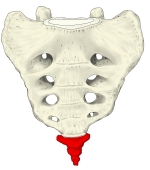

尾 骨 ( びこつ、英:coccyx )

・全体としては逆三角形の形を呈する。